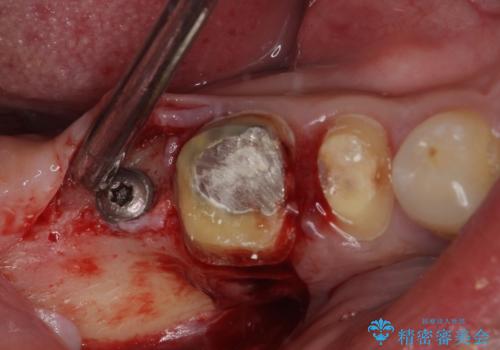

欠損している歯や、割れてしまって抜歯の必要な歯などがあり、咬合力が強いため欠損部はインプラント補綴を前提に治療を行うこととしました。

しかしながら、左下の抜歯部位は骨欠損が著しく大きく、多大な垂直的骨造成を要するため、3歯を支台としたブリッジによる補綴治療とし、右下のみをインプラント補綴としました。